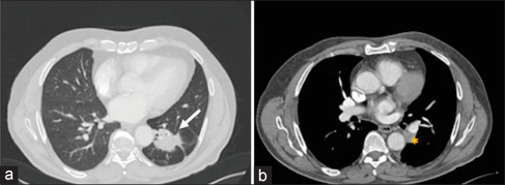

复杂的肺门解剖结构对胸外科医生来说可能是技术上的挑战,特别是在视频辅助胸外科肺叶切除术中。在这种情况下,为了防止出血并发症和转向开胸手术,提出了几种近端和远端血管控制方法。在此,我们提出了一种在具有挑战性的胸腔镜下左下叶切除术中对肺癌和叶间淋巴结病患者进行不必要的肺动脉阻塞和保留肺静脉的技术。

Complicated hilar anatomy may be technically challenging for thoracic surgeons, especially during video-assisted thoracic surgery lobectomy. In such instances, to prevent hemorrhagic complications and conversion to open thoracotomy, several methods of proximal and distal vascular control have been proposed. Here, we present a technique of unnecessary occlusion of the main pulmonary artery and preserved pulmonary vein during a challenging thoracoscopic left lower lobectomy in patient with lung cancer and interlobar lymphadenopathy.